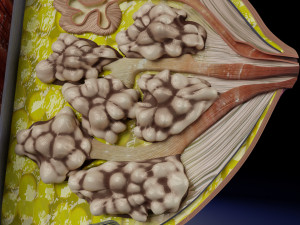

This is a 1:1 scaled model of right breast cut opened in sagittal plane to reveal its internal antomy and histology (schematic). The deeper parts and fascial layers are also depicted to give a very detailed approach to the model. The full layers starting from skin, nipple areola, till intercodtal muscles and ribs are also depicted.